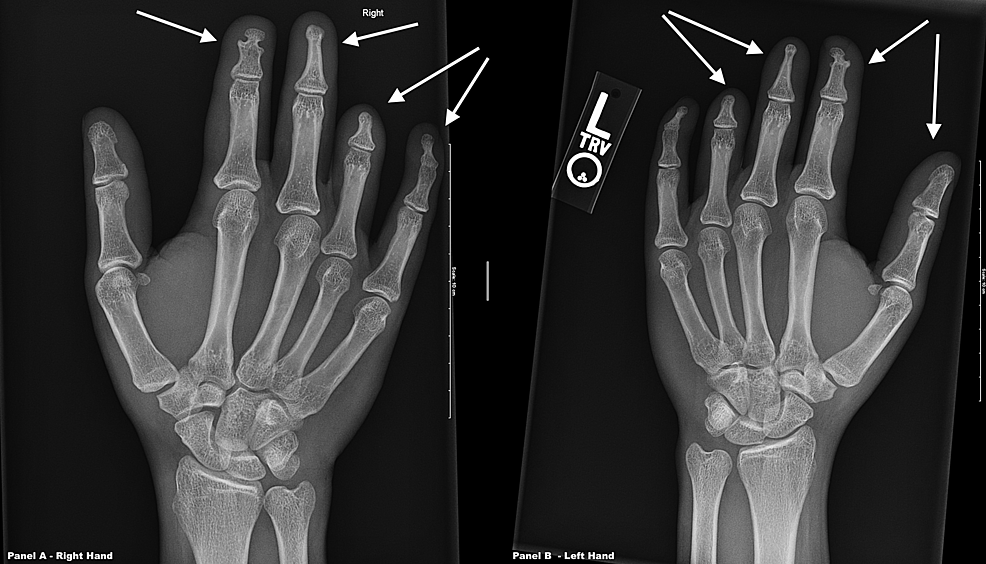

From radiologyinthai.blogspot.com

RiT radiology April 2011 Spade Hand Syndrome Type i (spade hand), type ii (mitten hand), and type iii (rosebud hand). Apert syndrome is a genetic disorder, characterized by deformities of the skull, face, and limbs affecting an individual’s health, daily. There are three main types of syndactyly in apert syndrome: Through multicenter collaboration, discussion among experts in the field, and evidence gathered from the literature, we. Apert. Spade Hand Syndrome.